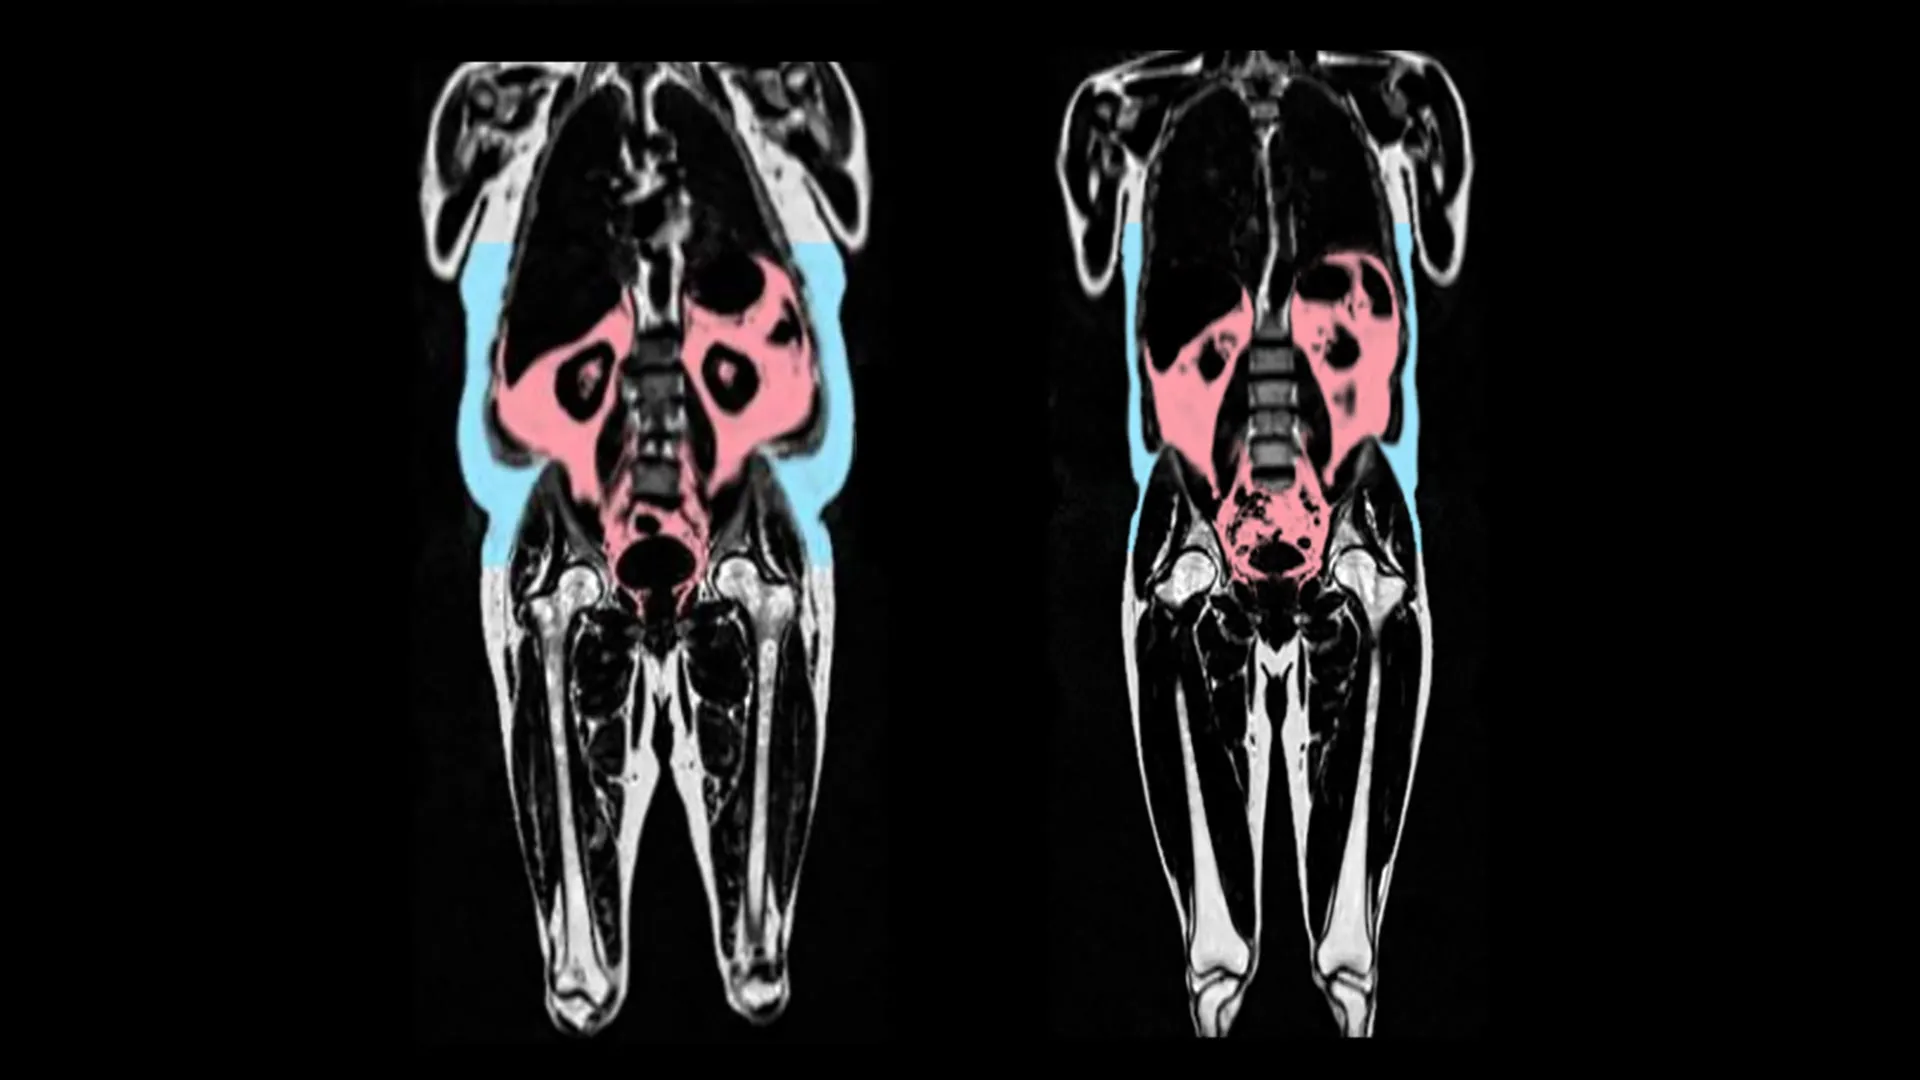

两张核磁共振扫描图,显示左侧的人拥有更多的内脏脂肪(红色)和皮下脂肪(蓝色)。图片来源:AMRA Medical

研究人员发现,心脏加速老化与拥有更多的内脏脂肪组织有关。内脏脂肪组织是位于腹部深处,聚积在胃、肠和肝脏等器官周围的脂肪。这种脂肪从外部无法看到,因此有些人即使体重正常,也可能有大量的内脏脂肪。